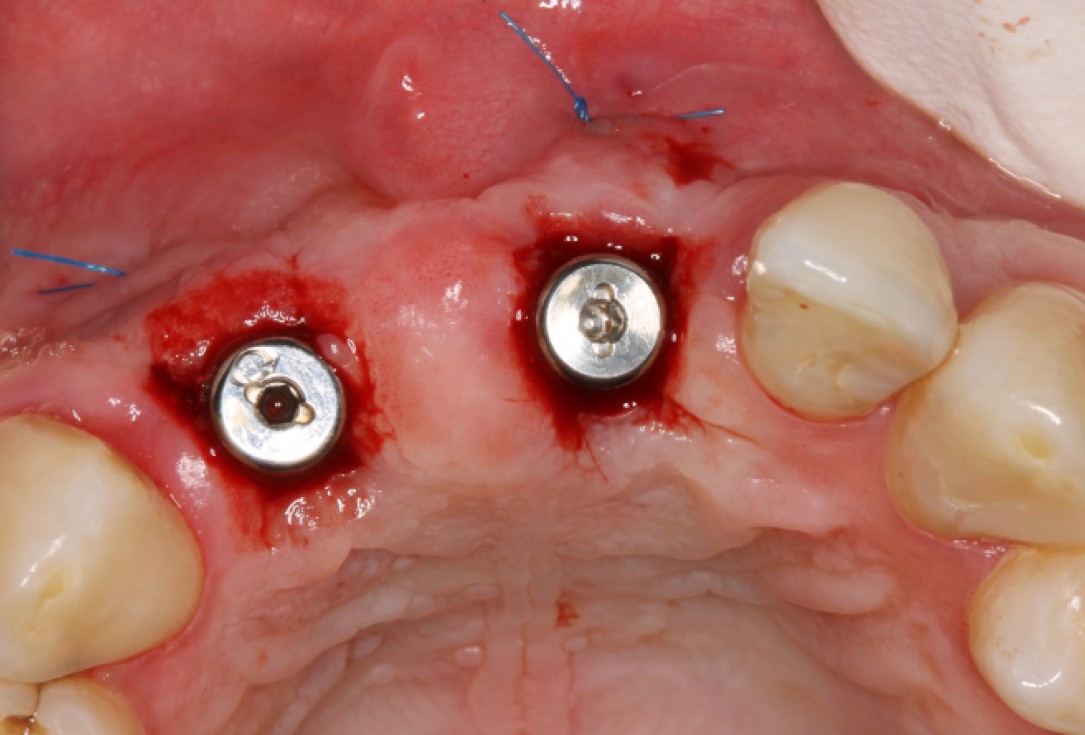

GBR and soft tissue augmentation with cerabone® and mucoderm® - H. Maghaireh & V. Ivancheva

Initial situation: missing teeth #11 & 12 and badly broken #21 root